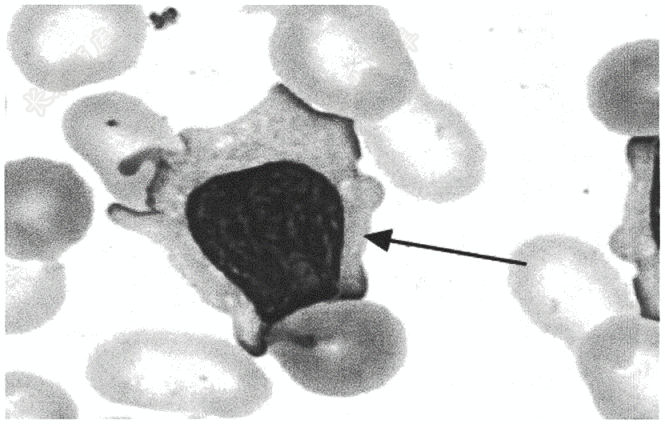

- 简答题请报告箭头所指细胞的名称